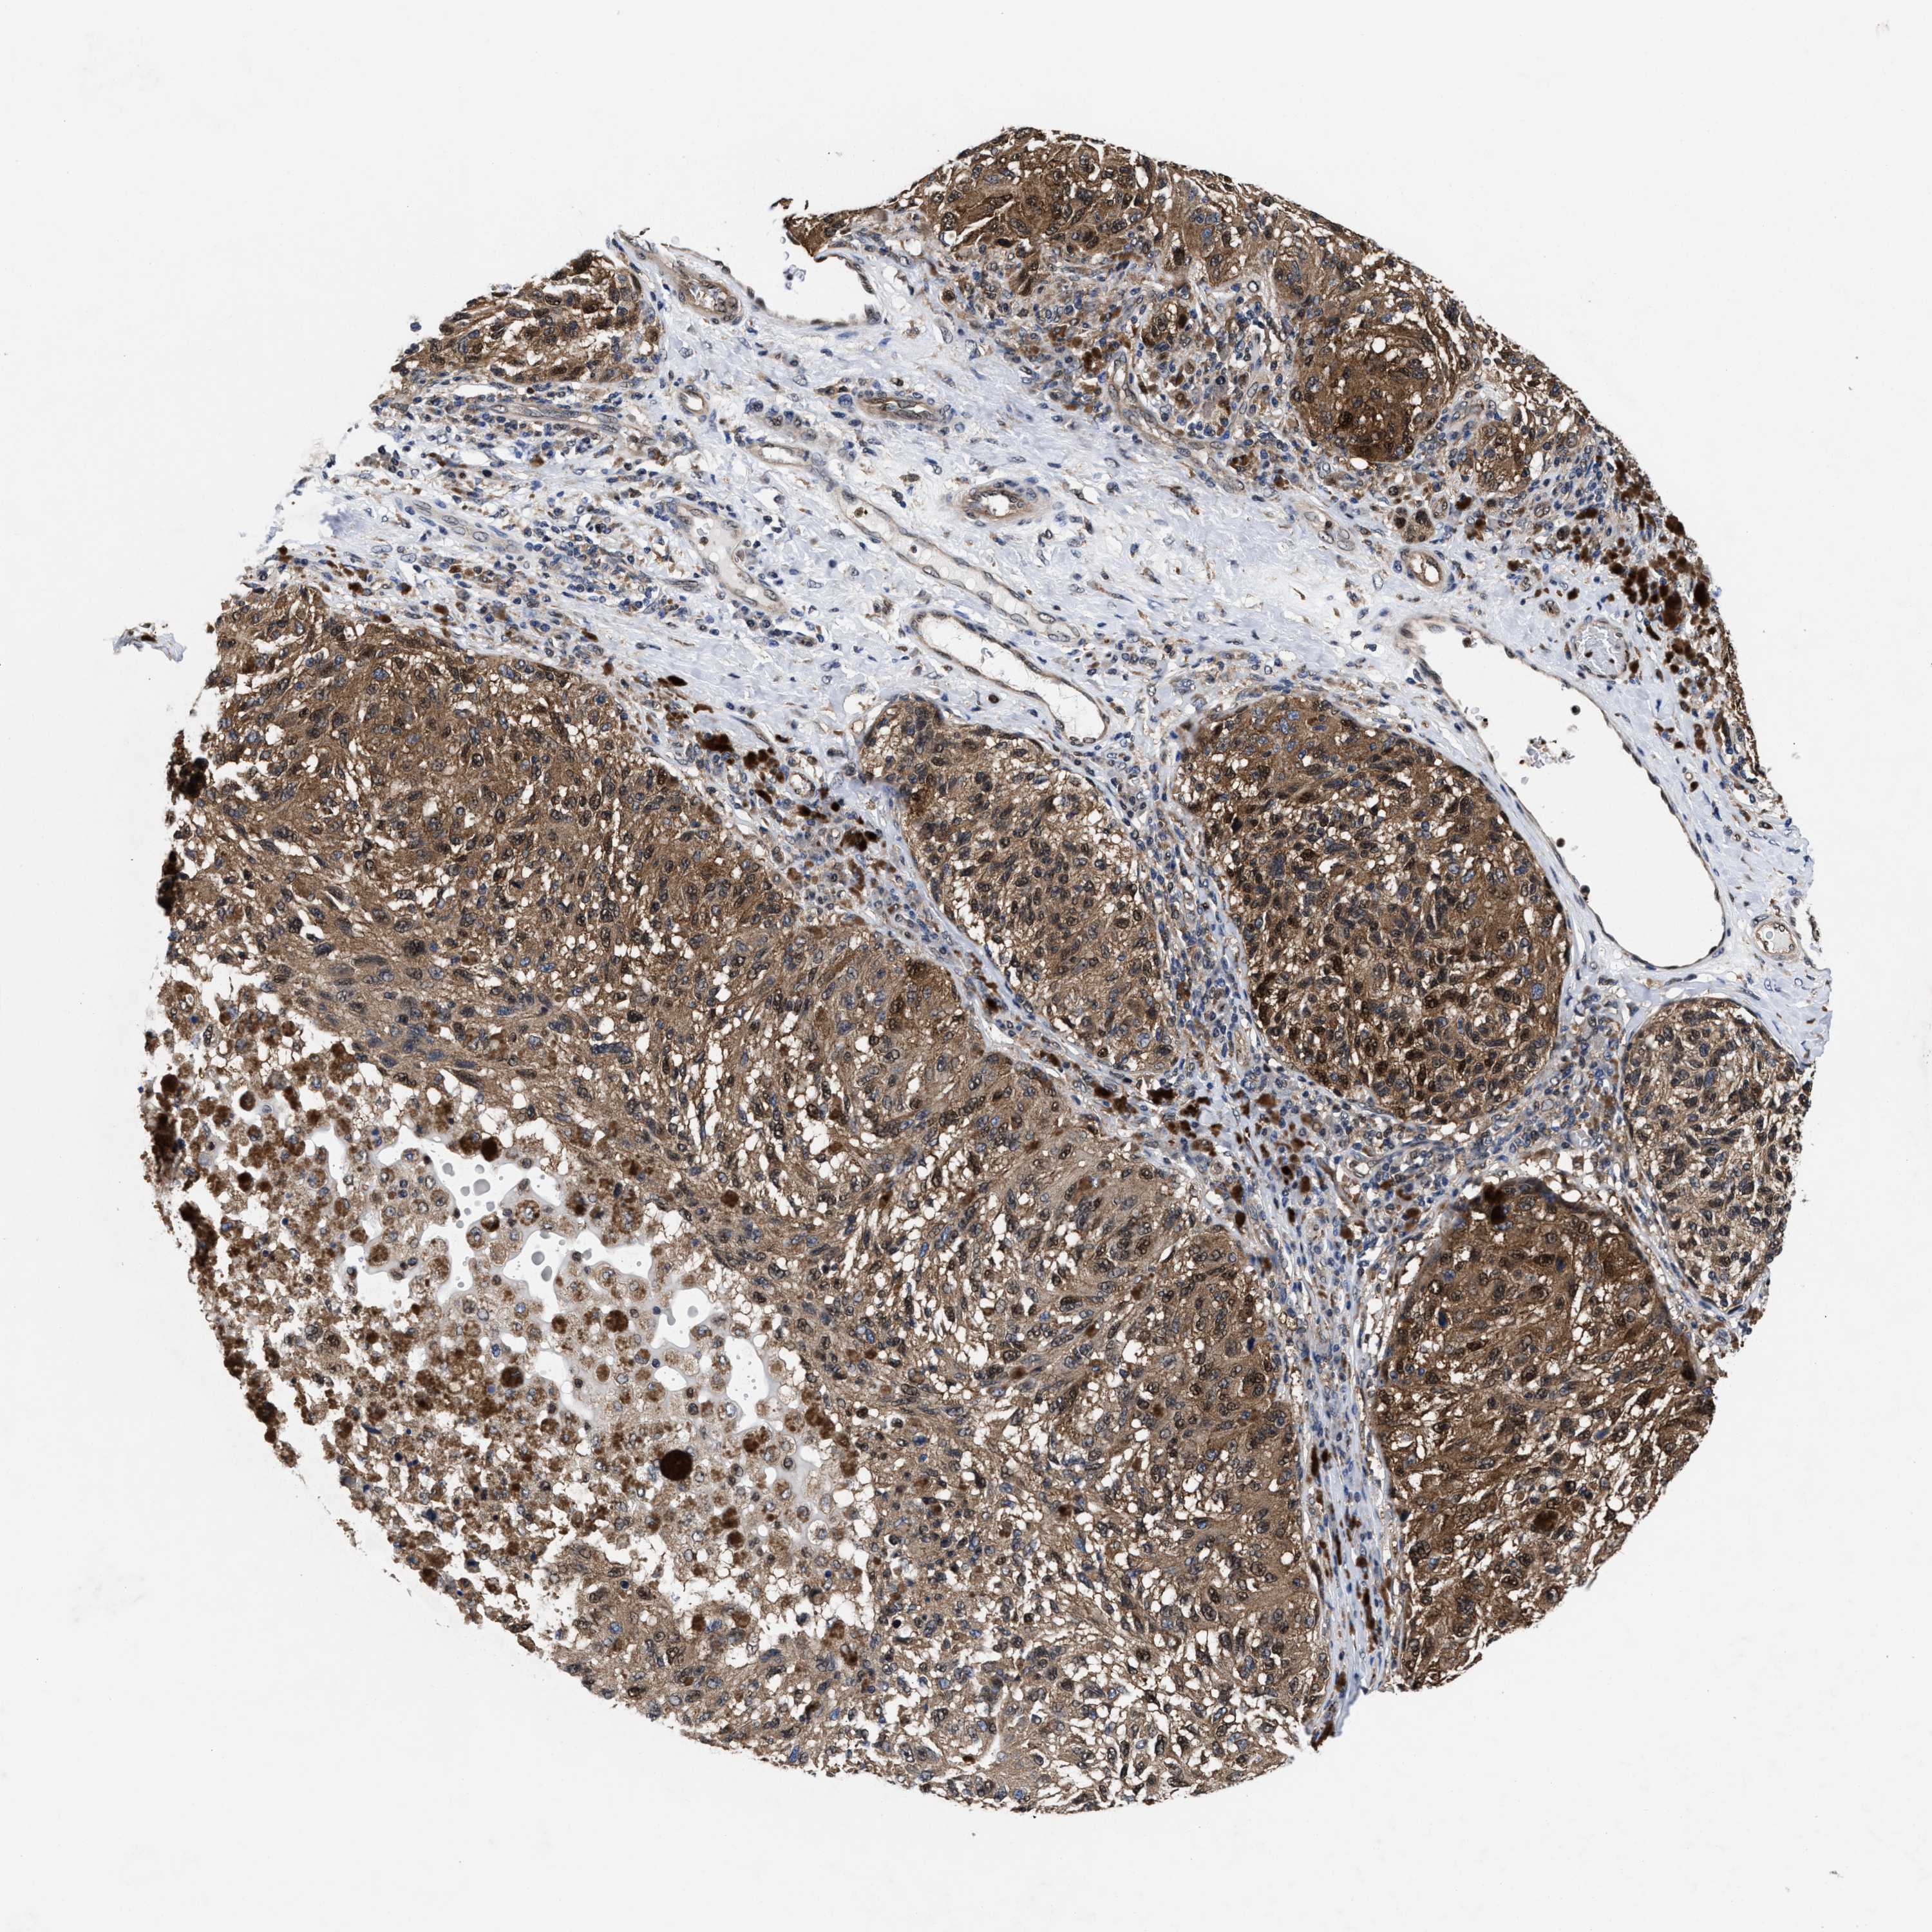

MELANOMA - Protein expressioni

A mouse-over function shows sample information and annotation data. Click on an image to view it in a full screen mode. Samples can be filtered based on level of antibody staining by selecting one or several of the following categories: high, medium, low and not detected. The assay and annotation is described here.

Note that samples used for immunohistochemistry by the Human Protein Atlas do not correspond to samples in the TCGA dataset.

Antibody stainingi

Antibody staining in the annotated cell types in the current human tissue is reported as not detected, low, medium, or high, based on conventional immunohistochemistry profiling in selected tissues. This score is based on the combination of the staining intensity and fraction of stained cells.

Each image is clickable and will lead to virtual microscopy that enables deeper exploration of all samples and also displays staining intensity scores, fraction scores and subcellular localization as well as patient and tissue information for each sample.

HPA022434

HPA022953

HPA022959

HPA028758

CAB007783

Staining

High

Medium

Low

Not detected

Intensity

Strong

Moderate

Weak

Negative

Quantity

>75%

75%-25%

<25%

None

Location

Nuclear

Cytoplasmic/membranous

Cytoplasmic/membranous,nuclear

Malignant melanoma, NOS

Malignant melanoma, Metastatic site